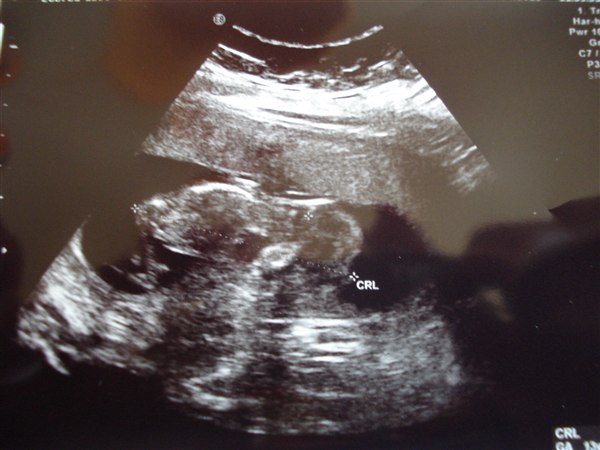

og lige på det første billede kunne vi allesammen med det blotte øje se, at nakkefolden var meget meget tynd. men så blev lægen så ivrig efter at vise os hvor fin den var, at han glemte at tage billede, så han måtte scanne og scanne og scanne og jeg måtte flere gange løfte bækkenet og vrikke med måsen og til sidst kom sygeplejersken og forsøgte og så fik de den endelig målt. da de så havde tastet alt ind i systemet udbrød de begge to "ja, det er meget, meget lavt!" og smilede over hele femøren. "din termin bliver rykket til 13. oktober (på Carlas fødselsdag) og din baby har det rigtig godt, tallet er 1:15000, det er en meget meget meget lille risiko"

nåhjo og så har den "en meget fin rygsøjle".

I får lige et par snapshots, den ligger ligesom på maven med hovedet ude til venstre: